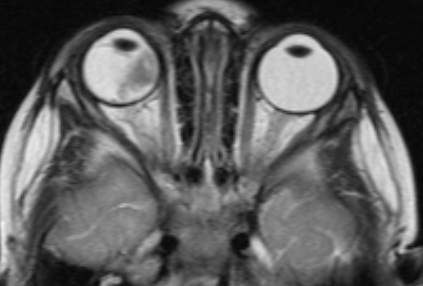

image002-1024x750.png

Рис. 1. Симптом «кошачьего глаза»